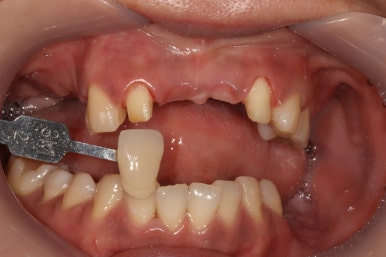

왼쪽위 처음 내원하셨을 당시, 오른쪽이 앞니 지르코니아 완성 후 정면 사진입니다.

보시면 파란색 화살표로 표시된 두 측절치에 기존에 치료받으셨던 PFM 브릿지의 경계가 드러나 회색 라인이 생기신 것을 보실 수 있고, 잇몸이 올라가버려 비교적 비 심미적인 모습인 것을 확인하실 수 있습니다.

지르코니아 브릿지로 교체함으로써 예쁜 첫인상을 완성해드렸어요.

이렇게 치료 중간에 환자분과 상의하면서 치아 색상을 적절히 채득해놓기에 가능한 일입니다.

본 환자분 같은 경우에는 자연스러운 치아 색상을 원하셔서 따뜻한 느낌의 색상으로 완성하였는데, 경우에 따라 보다 밝은 색상으로의 변화도 가능합니다! 연예인 라미네이트처럼요.